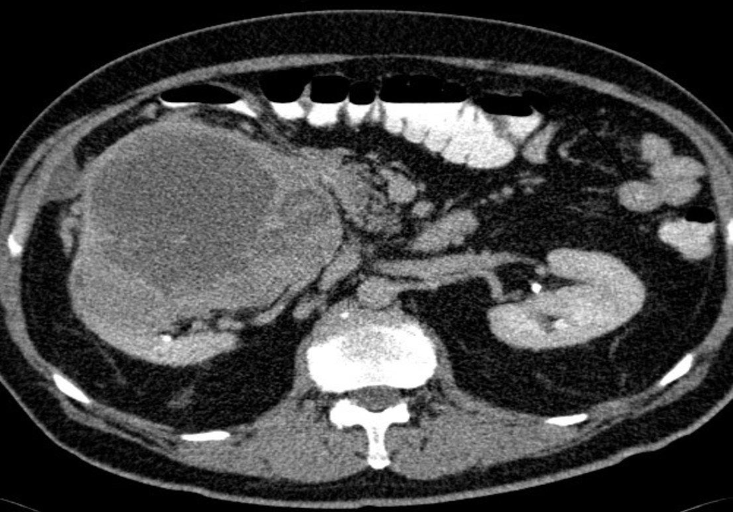

The patient had carcinoma of the bronchus.

CT scan of liver metastases. There are a large number of low density lesions in both lobes of the liver, which show enhancement around their edges.

LIVER METASTASIS

Imaging examination CT scan